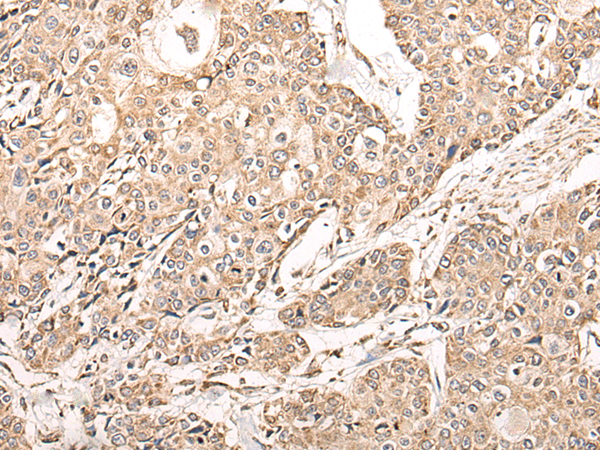

IHC positive control: |

Human lung cancer and human prostate cancer |